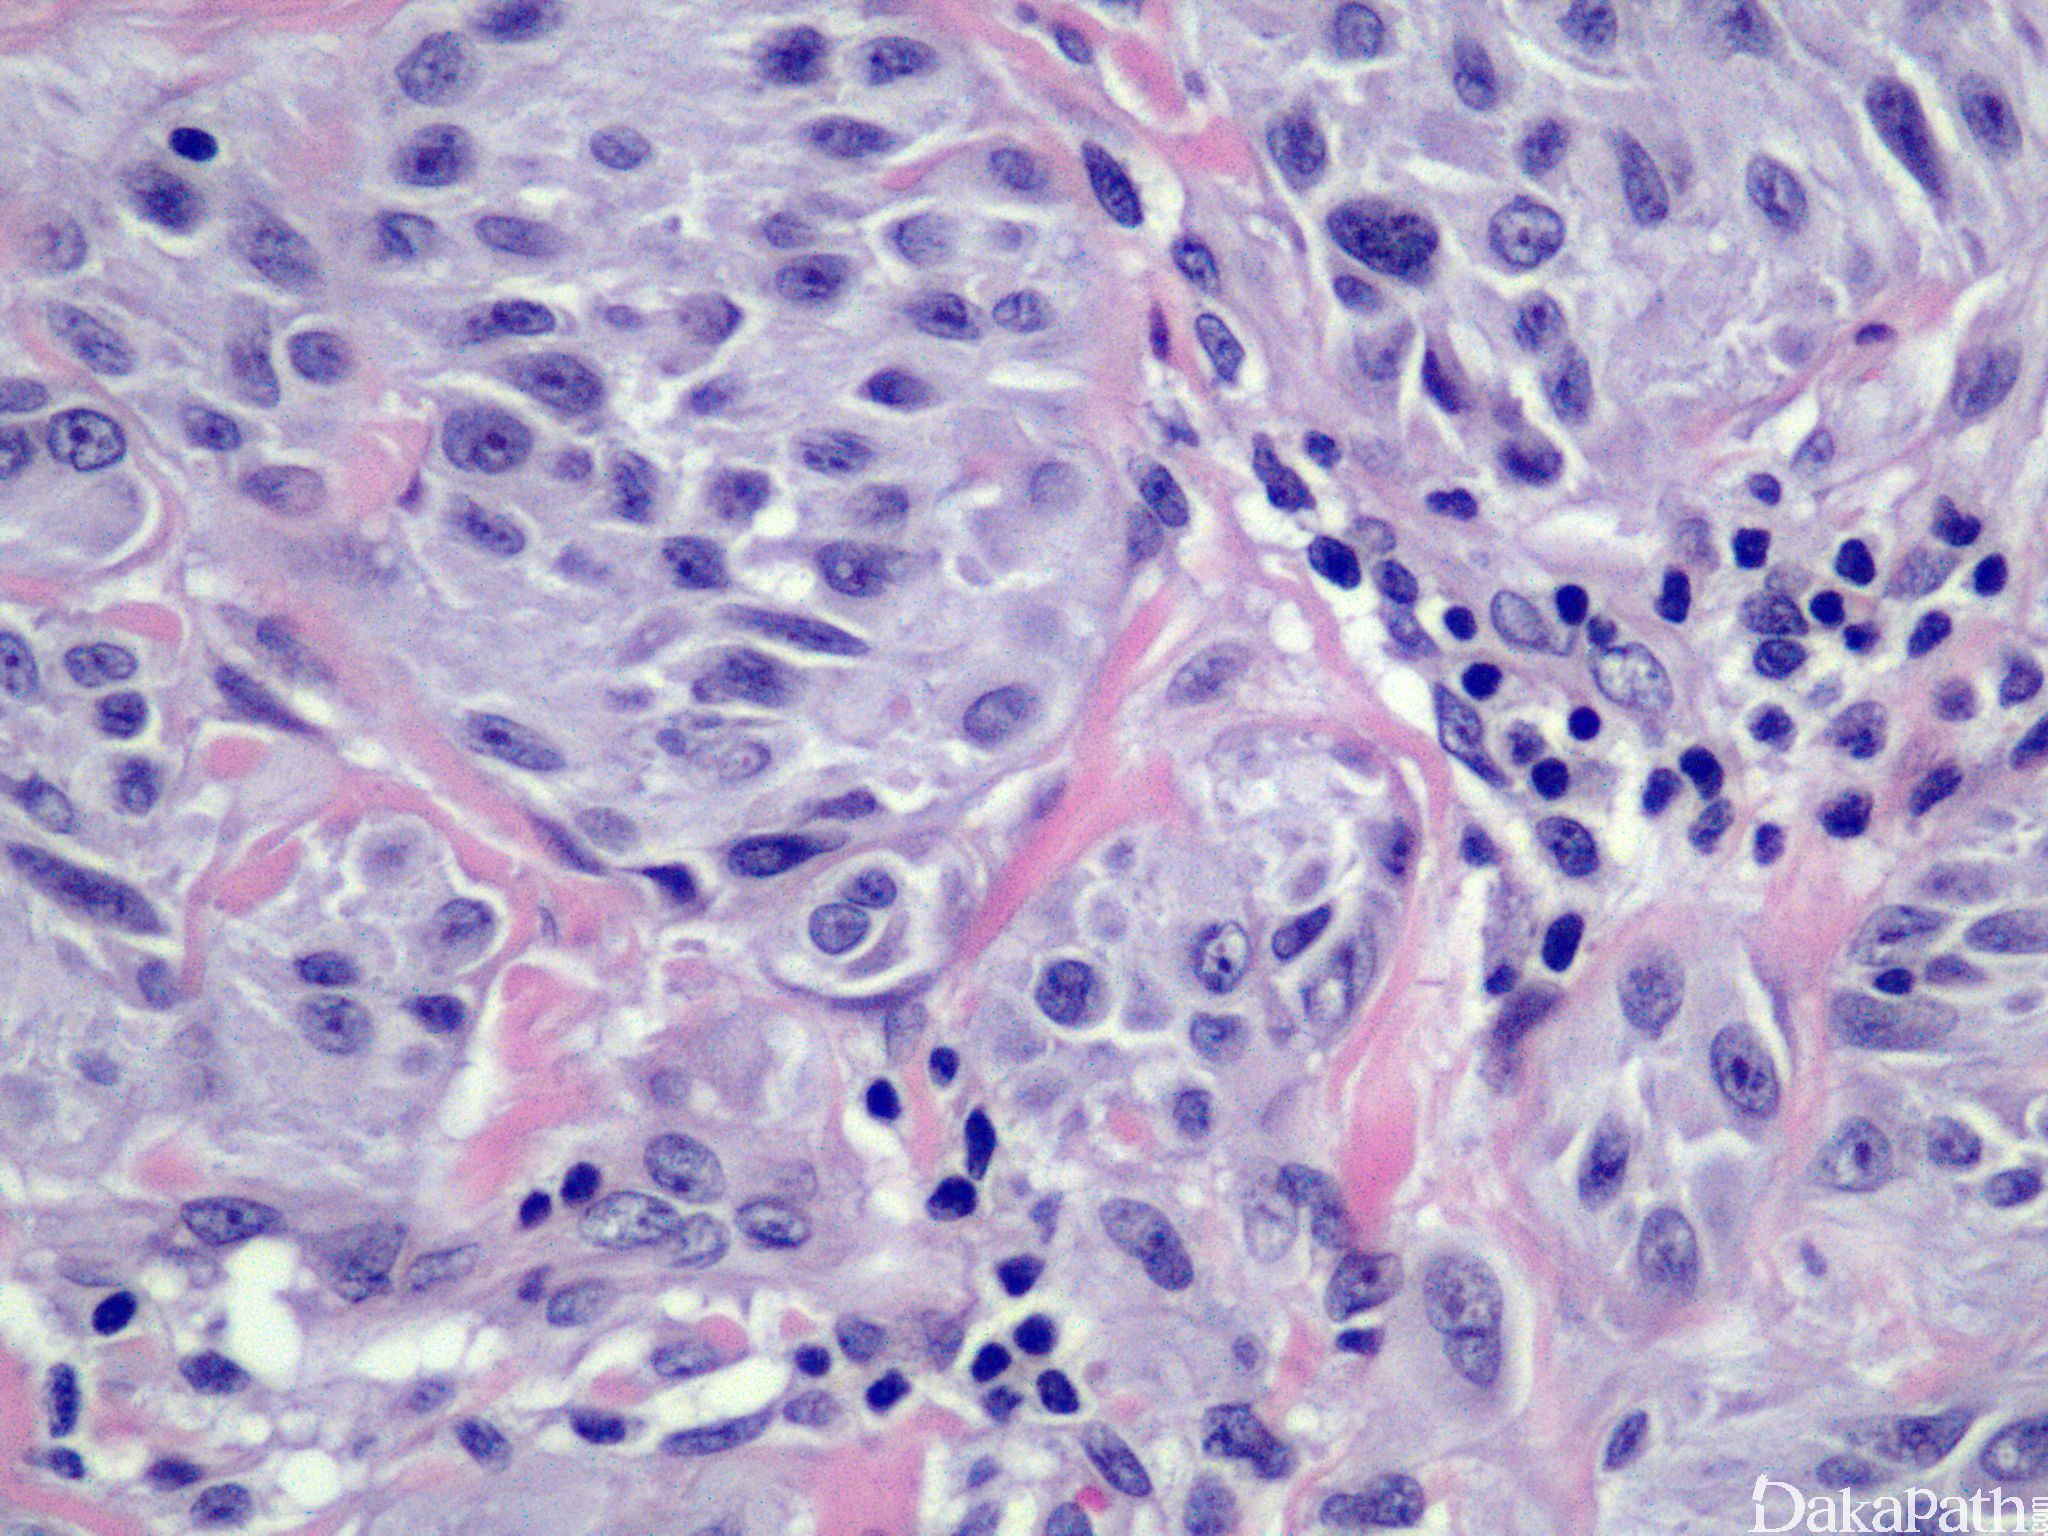

不典型 Spitz 痣

Atypical Spitz Nevus

交界性或复合型 Spitz 痣具有以下下特征之一,但不能满足恶性黑色素瘤的诊断标准者,可诊断为不典型 Spitz 痣:

不对称;

单个细胞为主(4mm 以上细胞巢较少);

溃疡;

真皮大片黑色素细胞;

真皮内成分无成熟表现;

深部可见核分裂像;

广泛累及皮下;

核多形性。